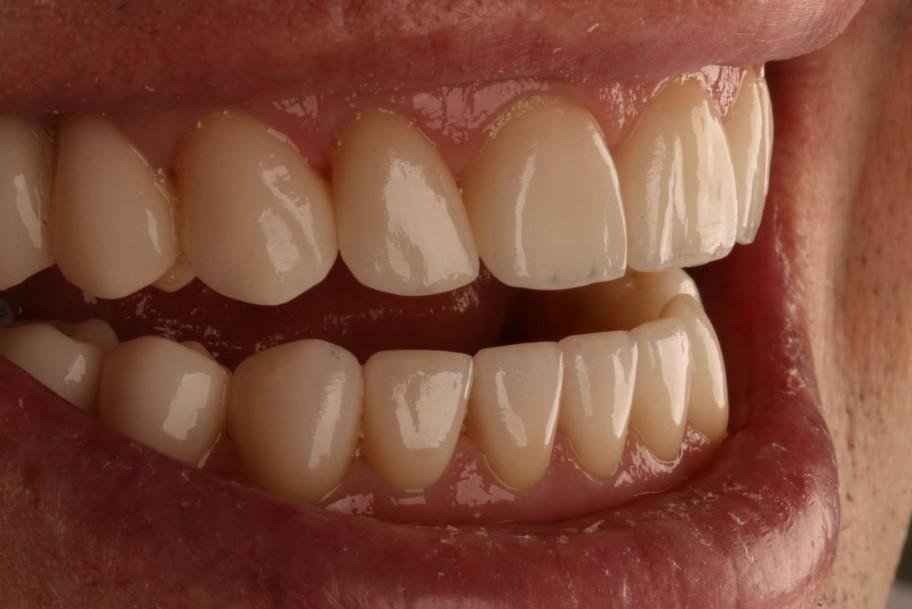

Как выглядел профиль пациента (фото)

К счастью, да. В «Белой радуге» мы можем сделать всё. Что-то быстро, например, вылечить кариес, что-то медленнее – это касается ортодонтии. Цена лечения будет зависеть от стадии. Но лично мне бы не хотелось видеть уже запущенный рот. Однако, увы, как раз он нам встречается чаще всего, ведь большинство стоматологических заболеваний на ранних стадиях протекают бессимптомно.

А когда люди обращаются за помощью, то получается долго и дорого. В некоторых случаях мне и другим нашим врачам приходится разбирать всю челюсть и собирать её заново.